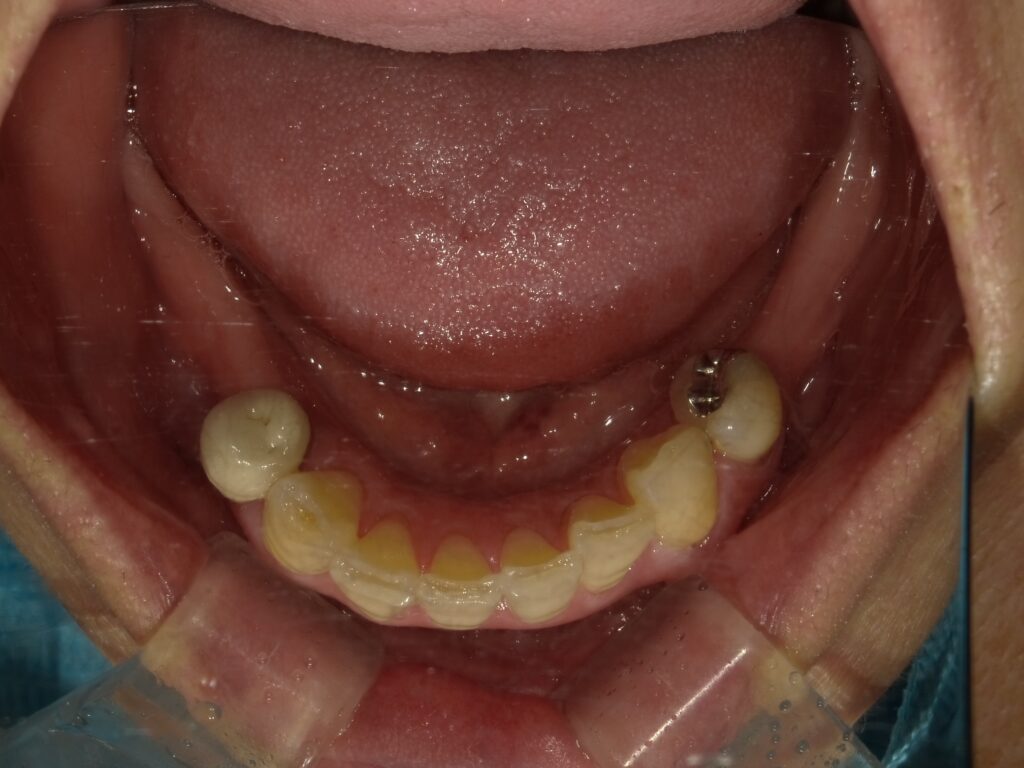

BEFORE

主訴

全体的に見た目を綺麗にしたい。奥歯でしっかり噛みたい。

診断名・主な症状

臼歯部欠損

年齢

65歳

治療内容

インプラント埋入(左下5・6,右下5・6,左上4・6)

サイナスリフト(左上4・6)

ジルコニアBr(右上6−左上3)

E –MAX CAD(右下4)

セラミックインレー(左下4)

治療期間/

約1.5年/約20回

インプラント治療 約2,000,000円

その他被せ物治療など 約1,000,000円

合計 約3,000,000円